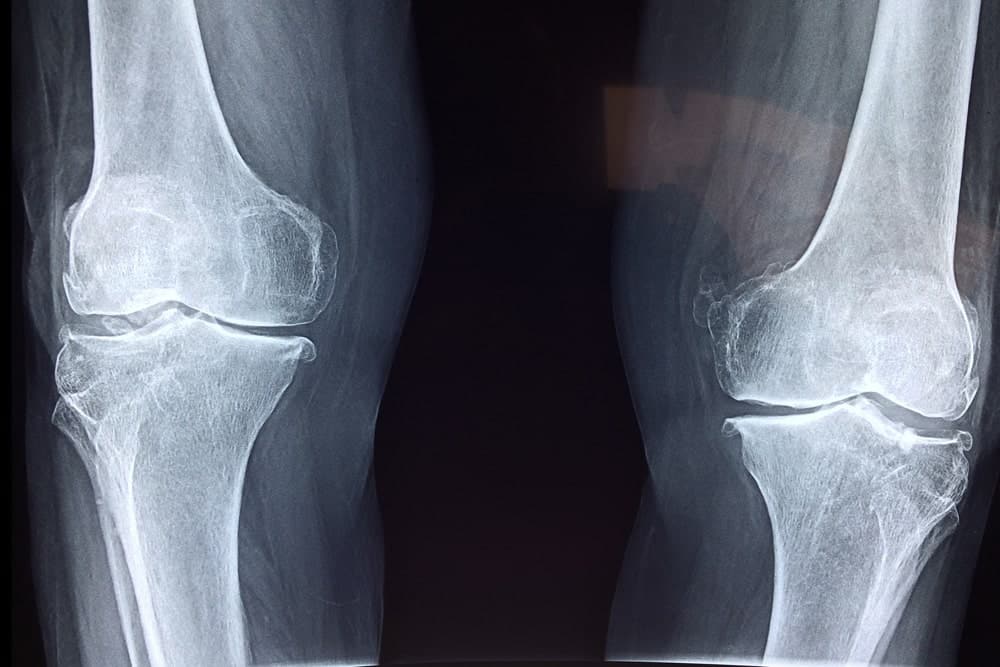

La artroscopia se utiliza principalmente en rodilla, hombro, cadera, codo, tobillo o muñeca. Y a través de esta intervención se pueden realizar diagnósticos o reconstrucciones (por ejemplo en el caso de un ligamento) y cirugías de reparación.